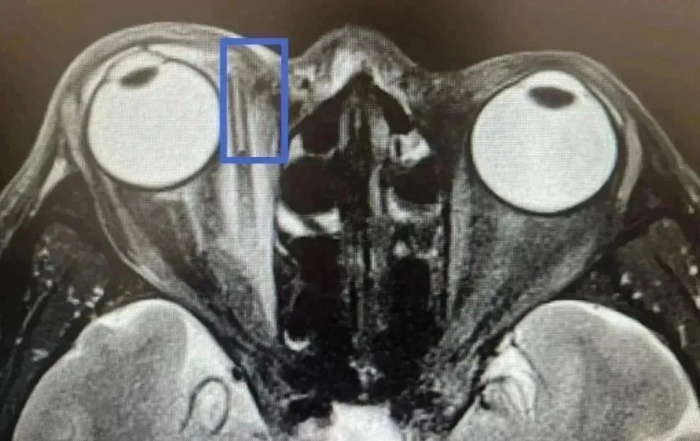

詳細(xì)詢問受傷過程時(shí),王老伯始終否認(rèn)有異物進(jìn)入眼里。但眼眶磁共振檢查顯示,王老伯右眼深處內(nèi)支肌旁有一長(zhǎng)條異物。

當(dāng)天,張宗端主任立即為王老伯施行眶內(nèi)異物取出+清創(chuàng)縫合術(shù),術(shù)中取出如筷子粗,長(zhǎng)約3厘米的樹枝。